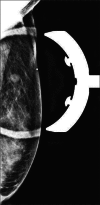

Figure 1.

Spot mammographic view of the left breast demonstrates a 7 mm ovoid mass at the palpable area of concern as designated by a radiopaque marker.